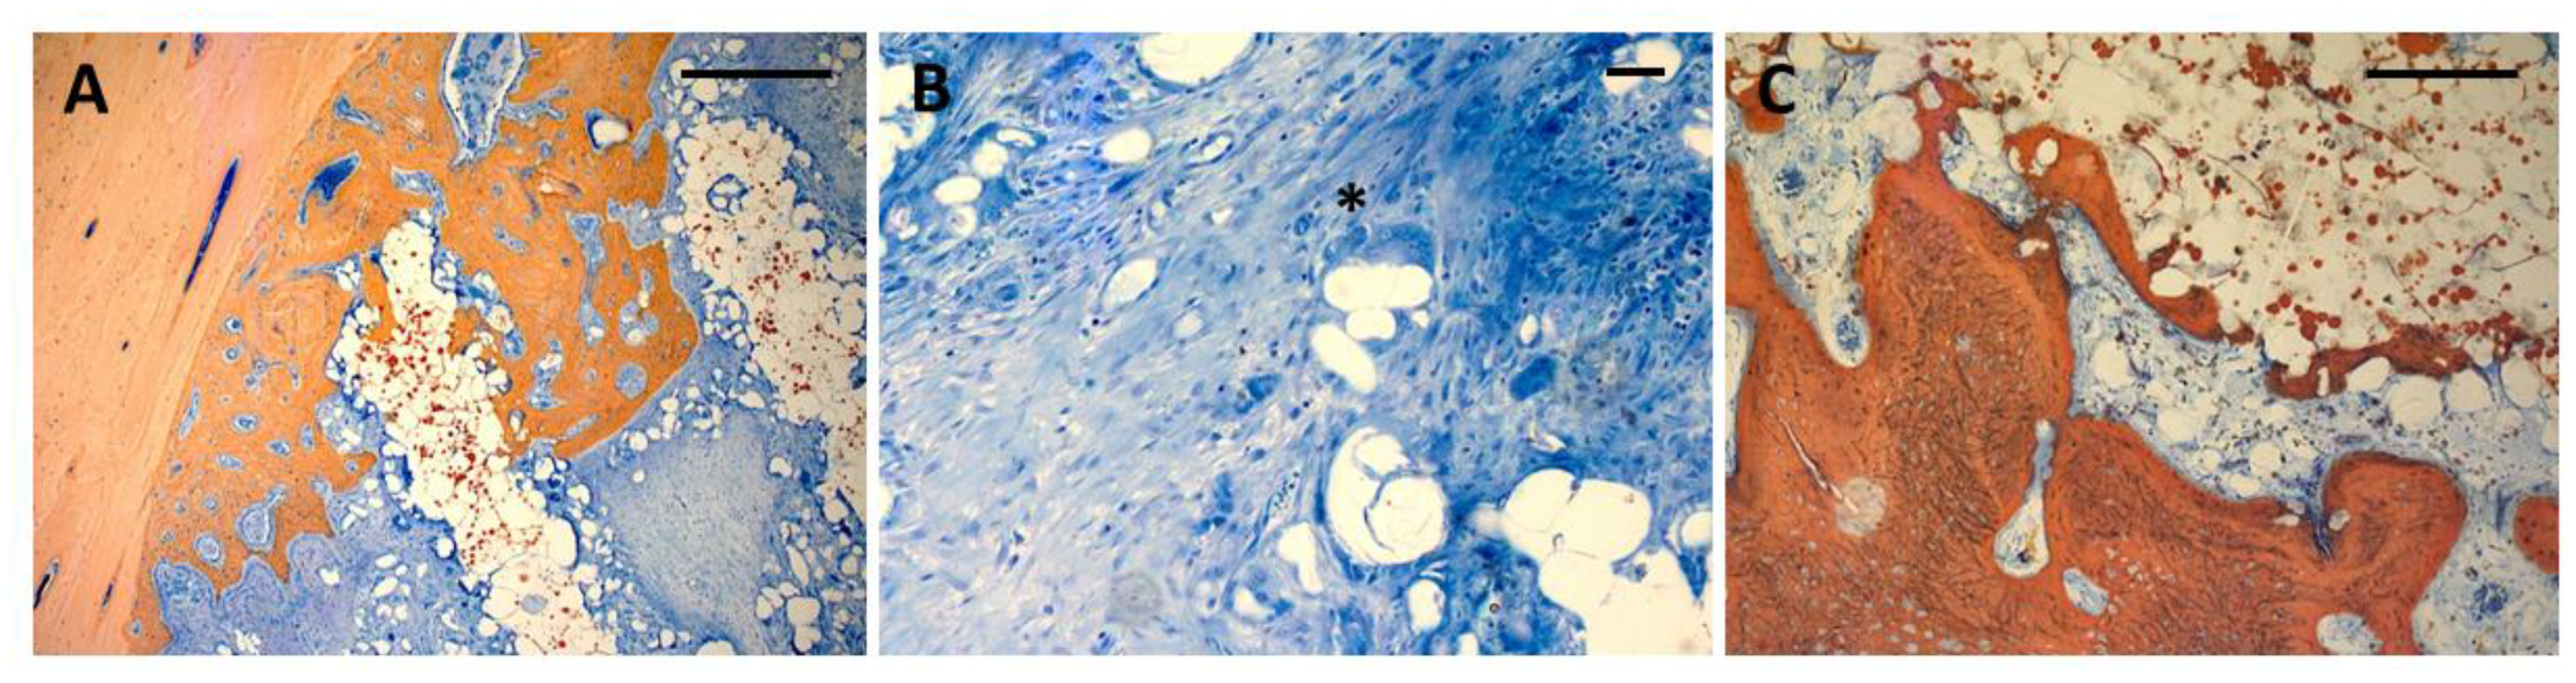

- surface staining for histomorphometric assessment of bone formation using Alizarine red / Methylene Blue and van Gieson stains.

3.1. Histology

3.2. Immunohistochemistry